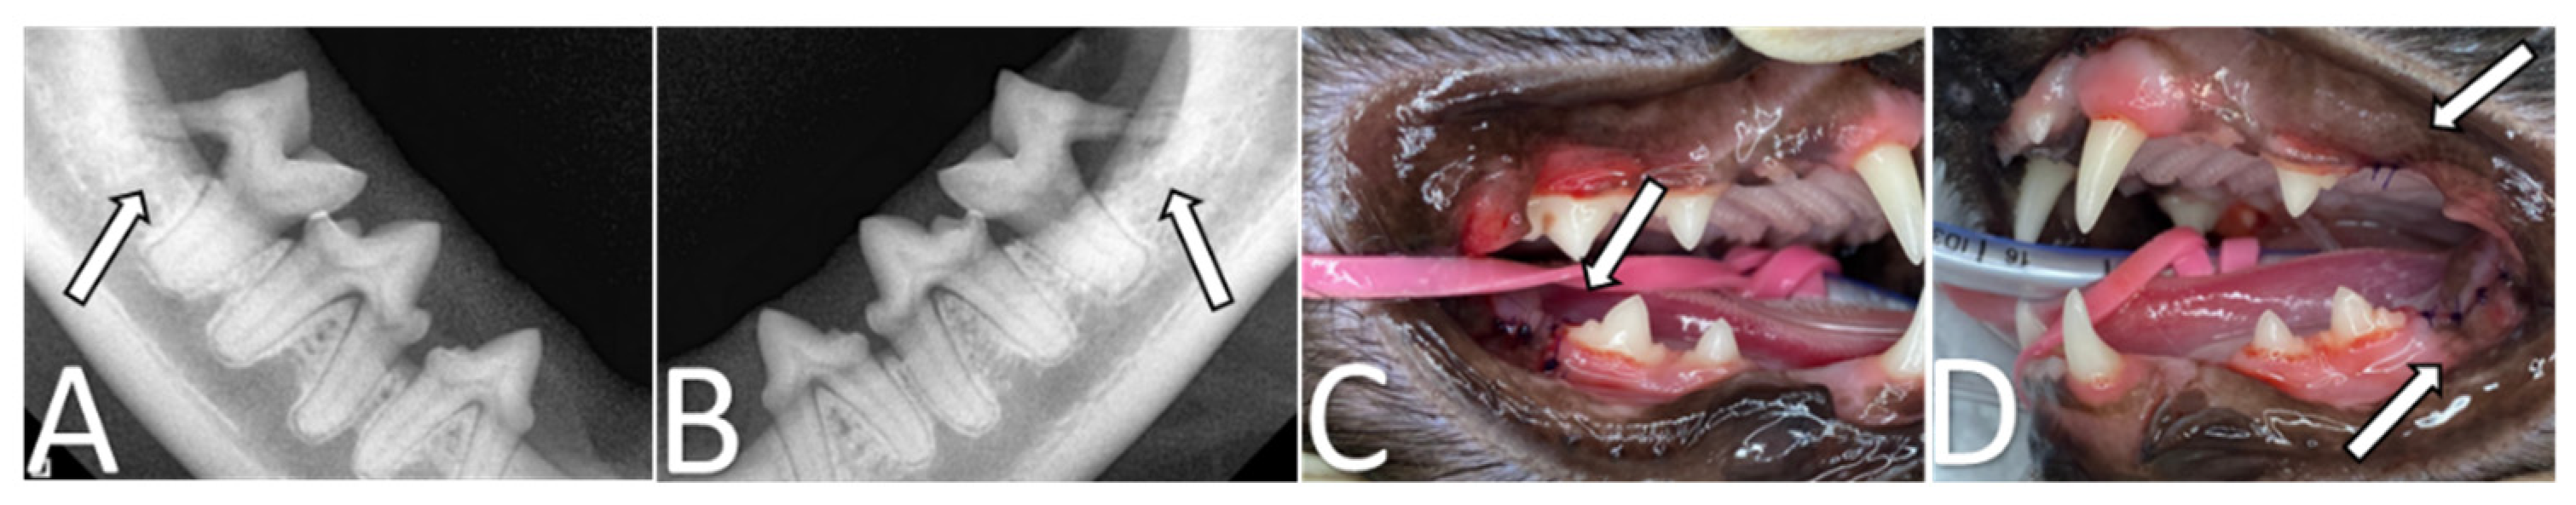

2. Case Presentation